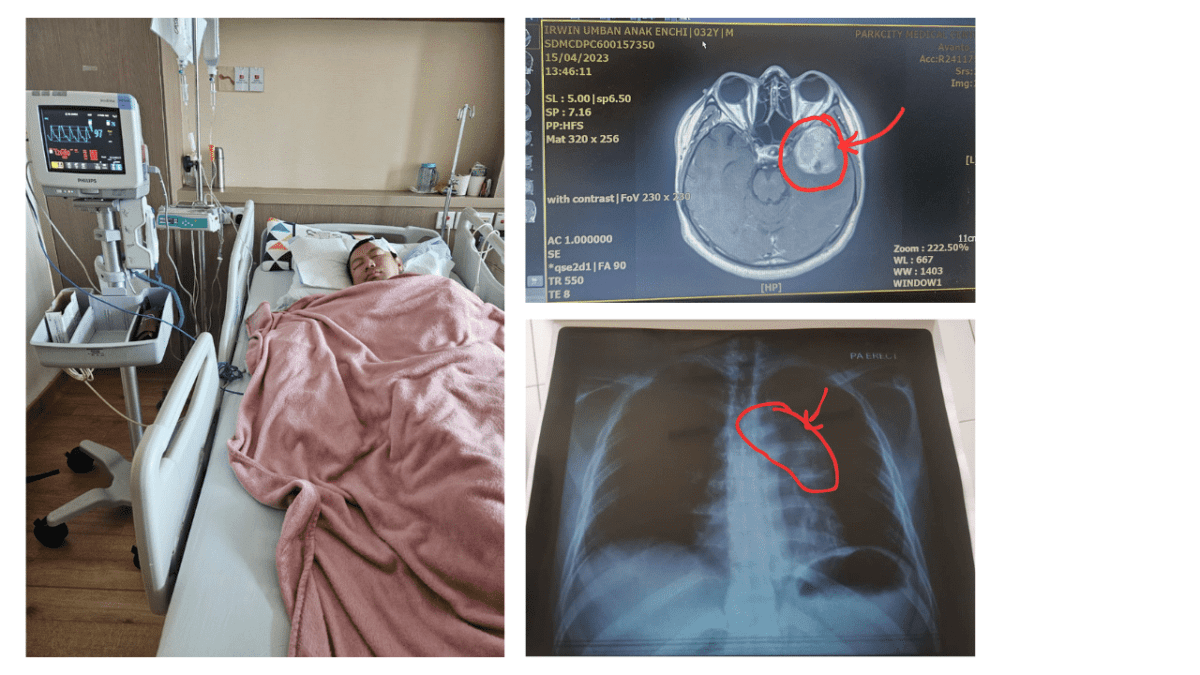

Just four months later, I began feeling abnormal pressure inside my head. A biopsy revealed that the same lymphoma had returned — this time, it had spread behind my eyeball, growing to the size of a golf ball.

April 2023 – Chemo Again

Once again, I was devastated. I began another round of chemotherapy — known as Salvage Chemo — and all the same side effects returned.